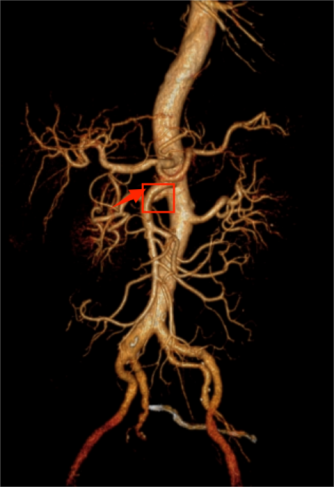

术前腹部增强CT:肠系膜上动脉近端血栓形成并闭塞